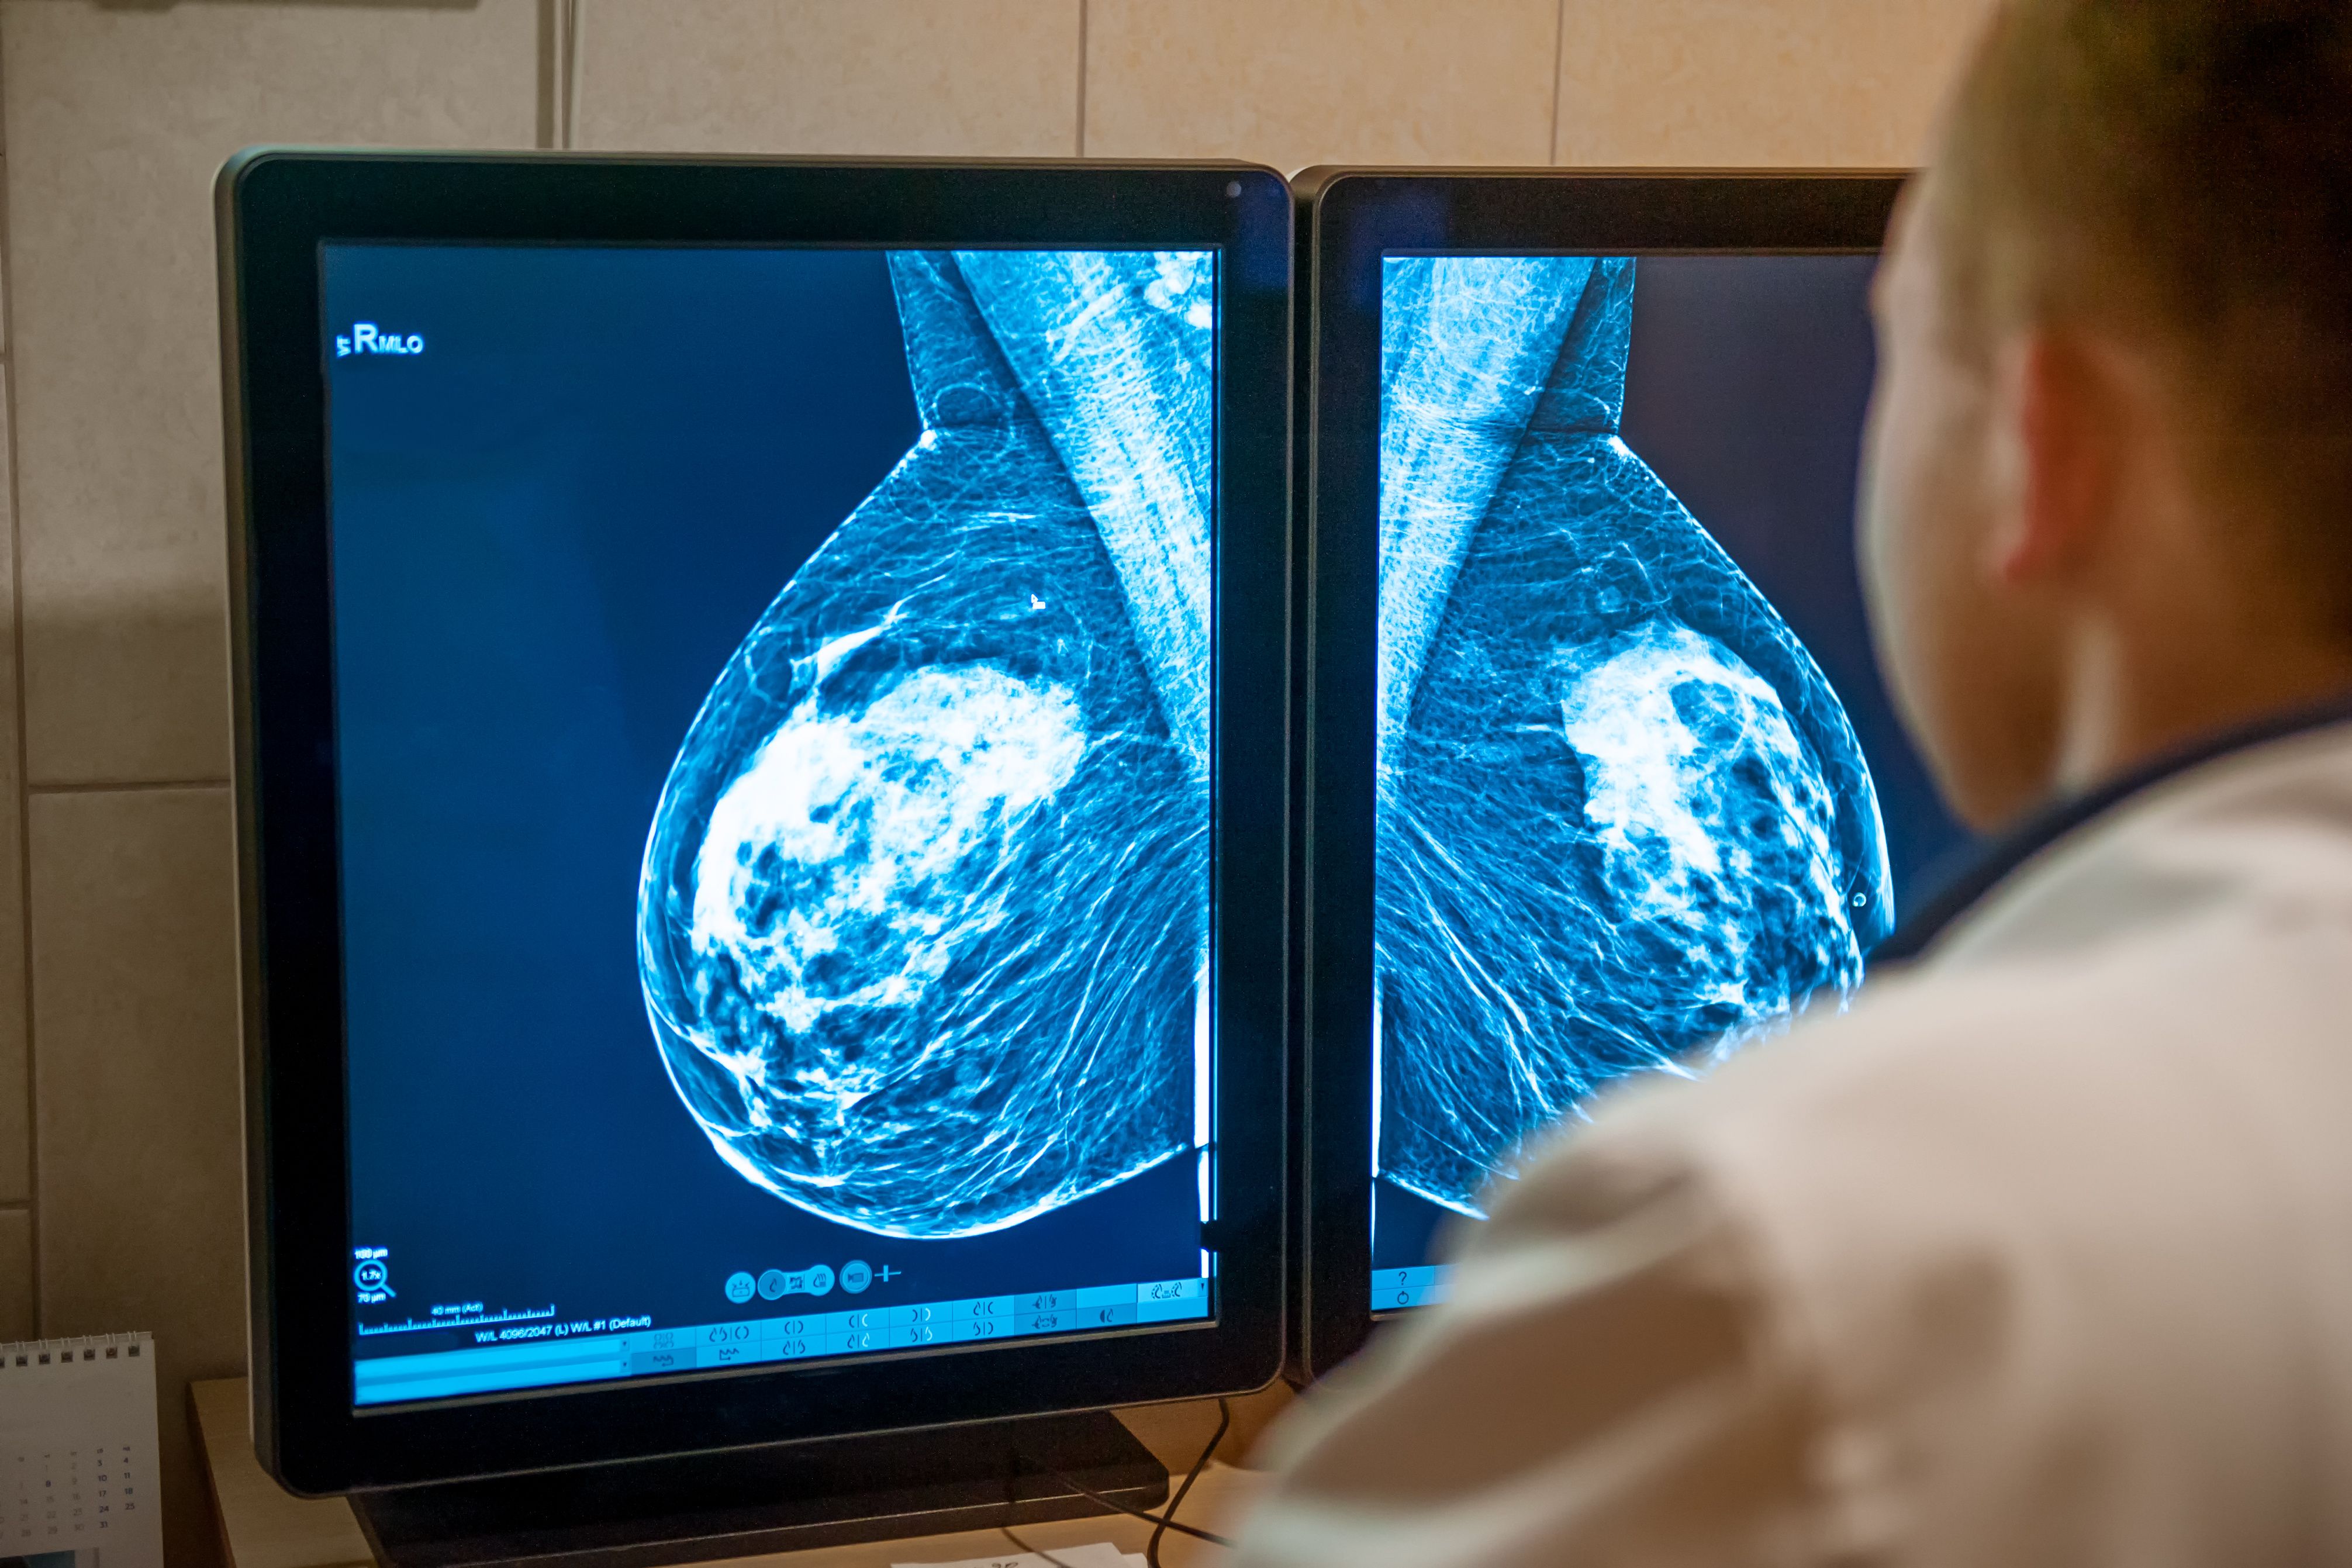

Supplemental molecular breast imaging improves cancer detection in dense breasts | Image Credit: © okrasiuk – stock.adobe.com.

Adding molecular breast imaging (MBI) to standard digital breast tomosynthesis (DBT) screening more than doubled the detection of invasive breast cancers among women with dense breast tissue, according to results from the multicenter Density MATTERS Trial published in Radiology and led by Carrie Hruska, PhD, of the Mayo Clinic.1,2

Dense breast tissue, present in nearly half of women in the United States, can obscure cancers on mammograms and increase the risk of delayed diagnosis. MBI, a functional imaging technique using technetium 99m sestamibi, highlights radiotracer uptake in metabolically active lesions, helping to detect cancers masked on mammography.